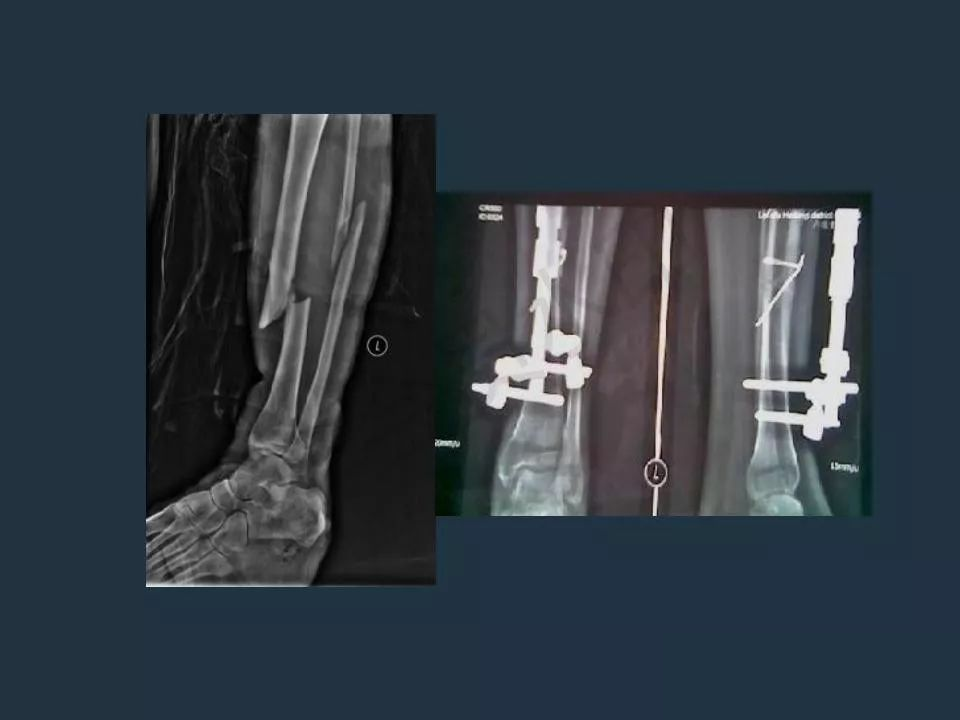

外固定支架技术治疗急诊骨折

骨科外固定支架